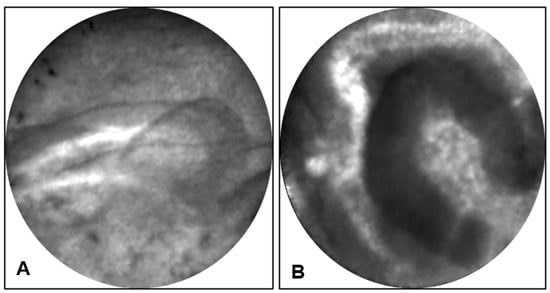

Endomicroscopy: EUS-nCLE of MCNs shows horizon-type epithelial bands (Figure 6A) of variable thickness without papillary conformation [23]. The epithelial bands are single or in multiple layers and are best observed when viewed tangentially to the nCLE probe. Further, MCNs can reveal clusters of inflammatory cells with areas of a dark background and fluorescent macrophages. Since MCNs may contain foci of atrophy and chronic inflammation, nCLE characterization of epithelial bands can sometimes be challenging during in vivo EUS. Inflammatory clusters of cells or debris can also be observed in pseudocysts, but such patients frequently have a history of pancreatitis and nCLE does not reveal any epithelial bands (Figure 6B,C).

Figure 6.

EUS-nCLE images of PCLs. (A) A mucinous cystic neoplasm revealing layering epithelial bands with thin epithelium in a lesion with low-grade dysplasia. (B,C) A pseudocyst revealing dark clumps of inflammatory debris (B) and a dark background (C) due to the absence of a vascular interstitium. (D,E) A serous cystadenoma demonstrating a fern-pattern of capillary network: The capillaries are packed with red blood cells (D) and partial contrast penetration highlighting the flow of red blood cells within the capillary network (E). (F) A cystic neuroendocrine tumor showing clusters of cells in geometric shapes (dark regions) separated by the stroma of the lesion.